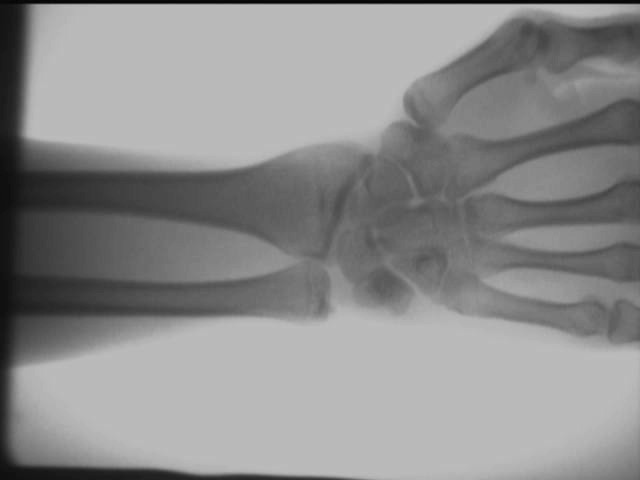

Efekat perspektive dlana

Efekat skočnog zgloba ruke

Efekat zgloba ruku

Gore navedeni rezultati ispitivanja se dobijaju na licu mesta korišćenjem AS-C200prenosivi rendgen aparat